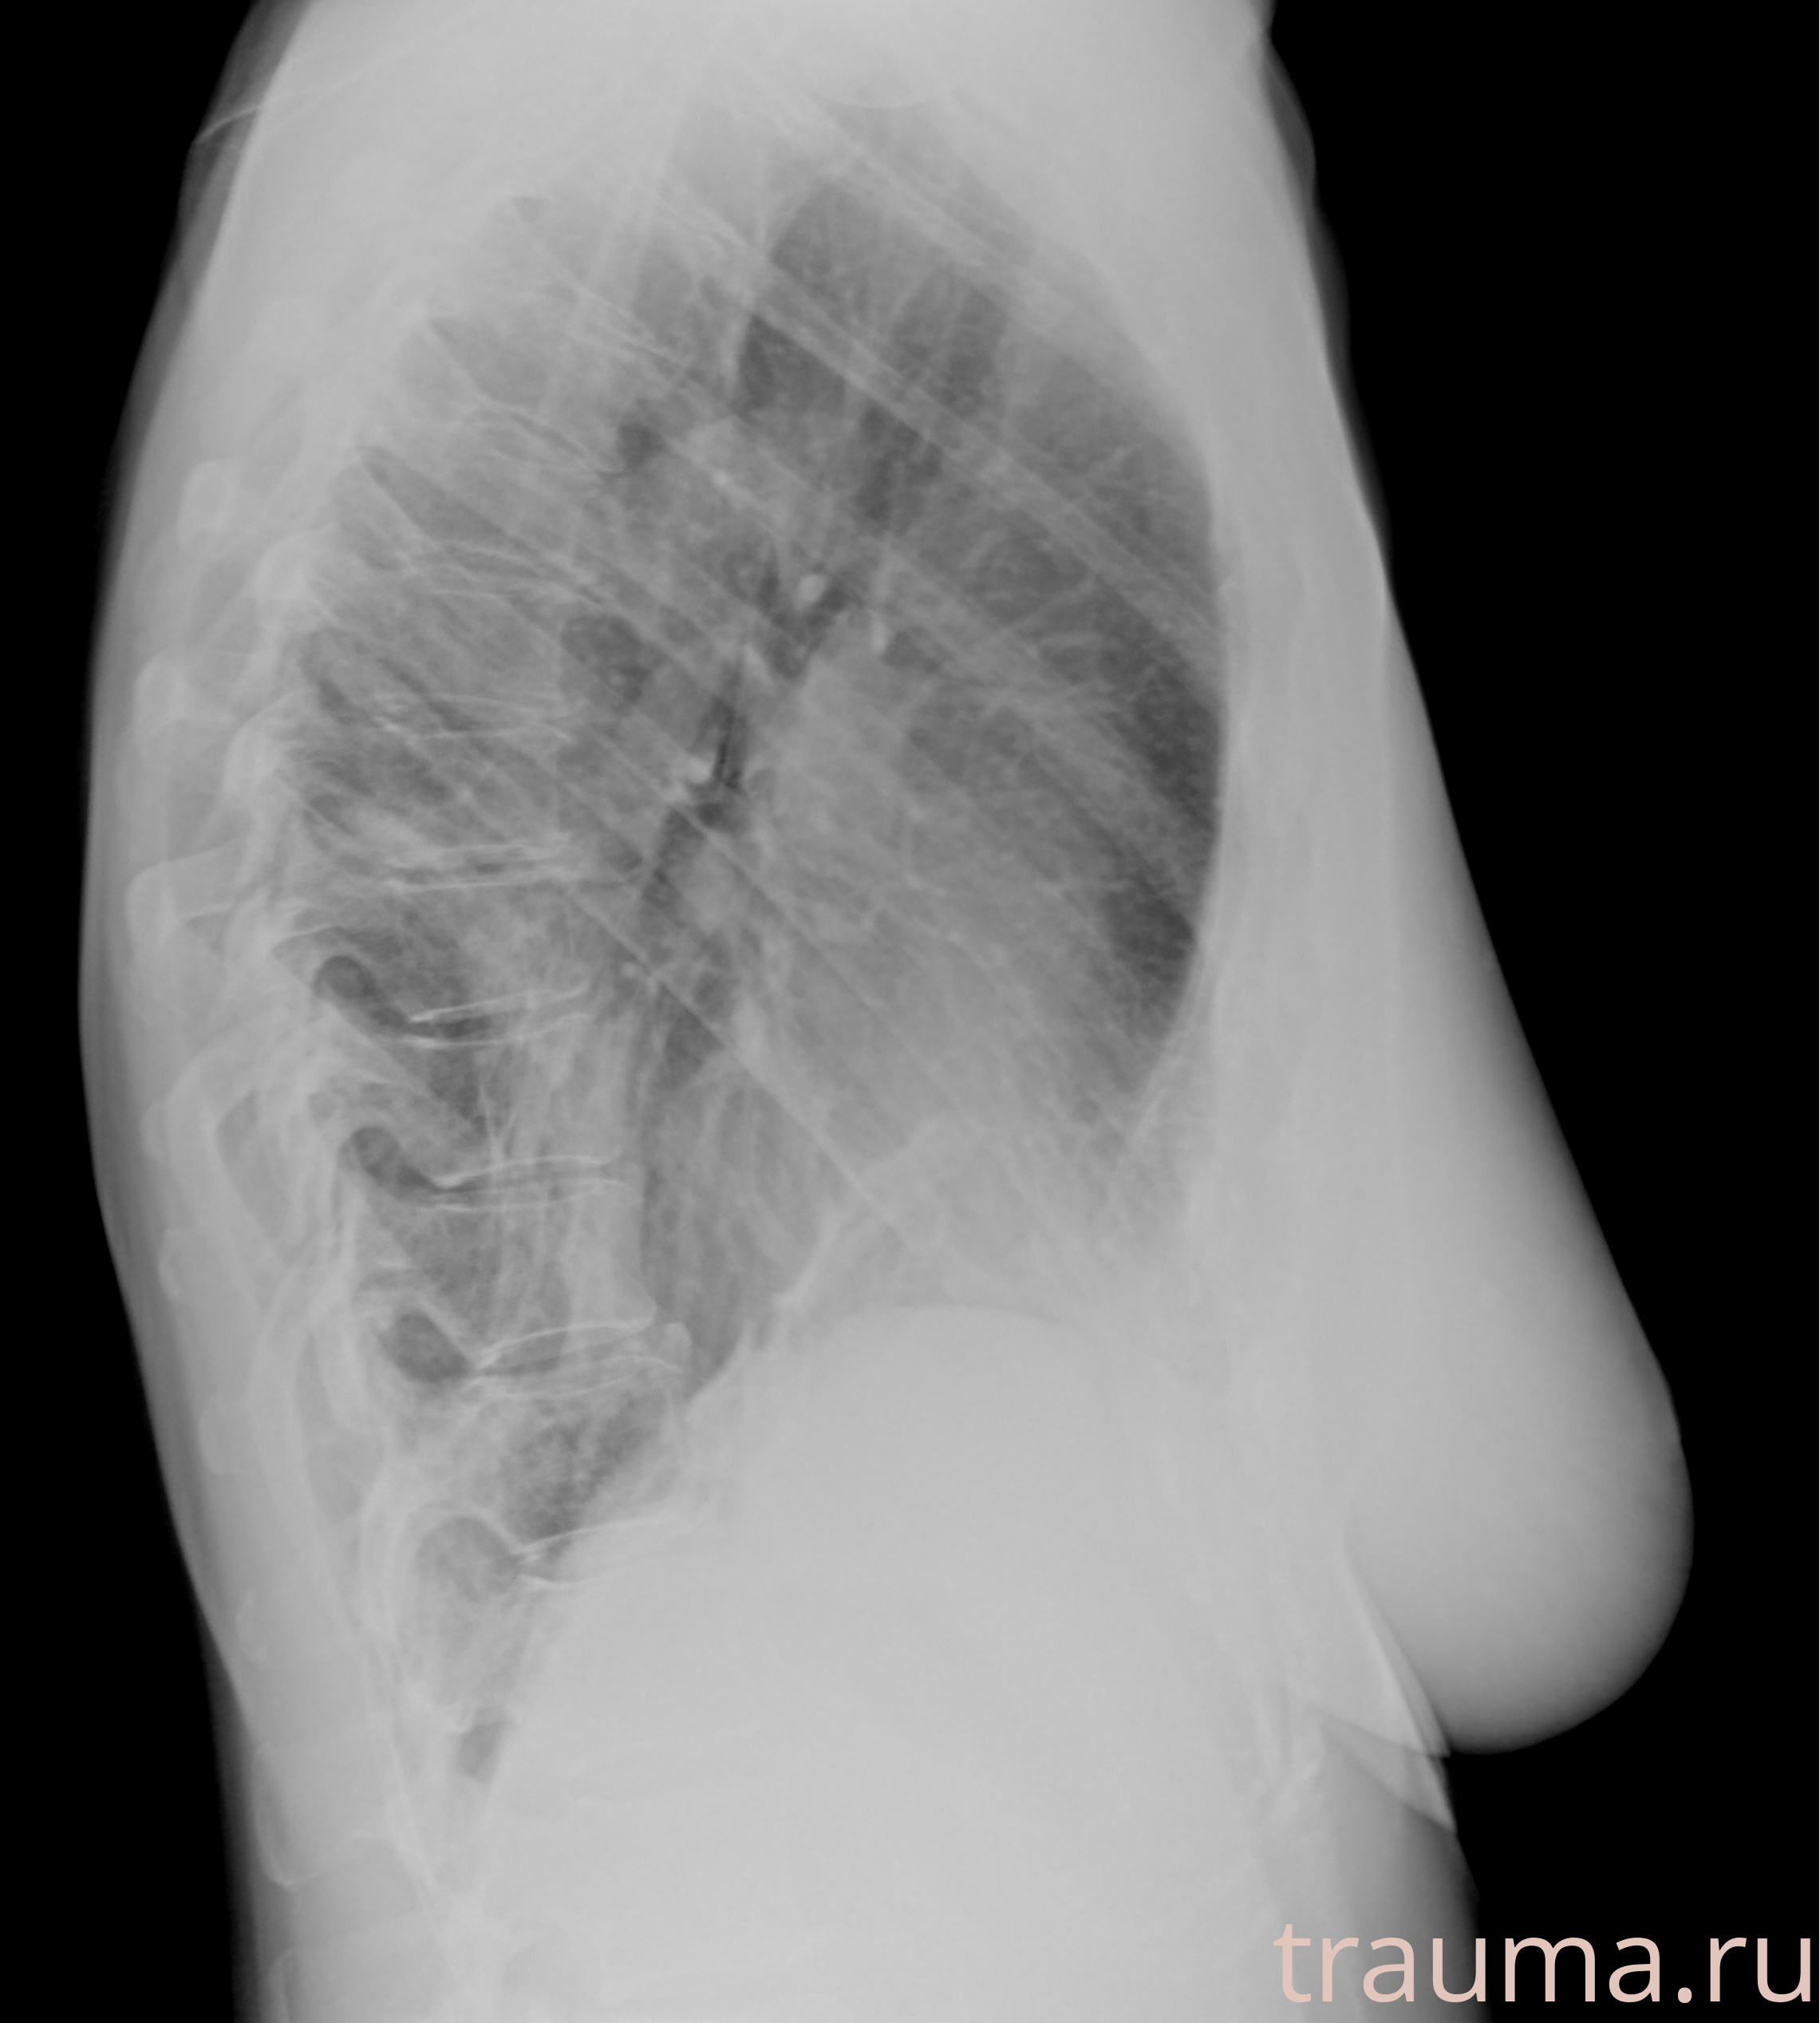

Рентгенограммы

Рентген на дому: по вашему адресу приезжает врач-рентгенолог, травматолог-ортопед с мобильным рентгеновским аппаратом, проводит диагностику травмы или заболевания, делает необходимые рентгенограммы, дает рекомендации по дальнейшему лечению. Получить качественные снимки в домашних условиях возможно благодаря уникальной методике, разработанной МосРентген Центром для института  Склифосовского

Яркость: 1   Контраст: 1   Инвертировать: 0 Увеличение: 1

Перетаскивайте мышь вверх/вниз для контраста, влево/право для яркости. Прокрутка колесом изменяет масштаб. Нажмите Сбросить для возврата к исходному изображению. При увеличении держите мышь в той области, которую хотите рассмотреть.